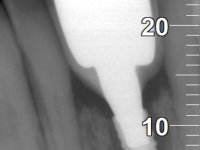

Female patient, 62 years old, smoker. 10 years ago, an implant had been placed in the area of teeth 41 and 42 to rehabilitate the lack of these two teeth with a two-element bridge. After the imaging exam, bone loss was observed next to the implant compatible with peri-implantitis. The buccal bone wall next to the implant showed extensive resorption, with the buccal surface of the implant in contact with the soft tissues and in a certain area a hole allowed the implant to be visualized through the gingival tissue. Teeth 42 and 32 already showed some mobility.

After an imaging study, the placement of two implants of 3.3 mm in diameter and 10 mm in length was planned. On the day of surgery, teeth 42 and 32 were extracted and the implant was removed. The implants were placed in the area of the alveoli, taking care to slightly lingualize their positioning. An impression was made using the open tray technique with the flap open for the fabrication of the immediate provisional bridge. While the impression was taken to the laboratory, tall healing screws were placed and the surgical wound was sutured. The patient waited 2 hours in the waiting room while the temporary bridge was made in the laboratory. An immediate screw-retained provisional bridge was placed and its seating was controlled by imaging. After 3 months, the final impression was made using an open tray technique. In this consultation, we took the opportunity to polish the temporary bridge with rubber cups so that the soft tissues could mature in better conditions. Information was collected to better characterize the monolithic structure in Zr. Color guides were used for the coronal and gingival ceramics. In the laboratory, a bridge was made in Zr. bolt-on that has been carefully characterized. After approval by the patient, it was definitively placed in the mouth. Tightening was performed with a dynamic wrench with a torque of 35 N. The holes were covered with Teflon and filled with composite resin.